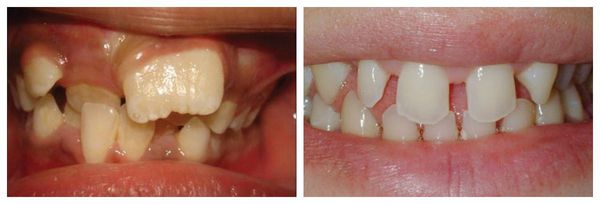

W przypadku makrodoncji (macrodontia) dochodzi do powiększenia jednego lub kilku zębów, co powoduje brak wystarczającej ilości miejsca w łuku zębowym. W efekcie inne zęby ulegają przemieszczeniu, a łuki zębowe deformują się i tracą prawidłowy kształt. Taki stan często prowadzi do stłoczenia zębów, zaburzeń zgryzu oraz problemów z prawidłowym żuciem.

Przy mikrodoncji (microdontia) sytuacja jest odwrotna — zęby (pojedyncze lub kilka) są mniejsze niż norma, co skutkuje powstawaniem przerw między nimi (szpar, diastem). Zęby mogą mieć również stożkowaty kształt, a nadmierne odstępy wpływają na estetykę uśmiechu, fonetykę oraz prawidłowe rozłożenie sił żucia.

Makrodoncja (po lewej) i mikrodoncja (po prawej)

Niedopasowanie rozmiaru zębów do wielkości i kształtu szczęki może prowadzić do licznych zaburzeń okluzyjnych, czyli wad zgryzu (anomalii zgryzowych). Zarówno mikrodoncja (microdentia), jak i makrodoncja (macrodontia) powodują nieprawidłowe rozmieszczenie zębów w łuku zębowym i zaburzają równowagę między szczęką a żuchwą.

• Stłoczenie zębów (stłoczenie łuku zębowego) – zbyt mała przestrzeń w łuku zębowym powoduje, że zęby zachodzą na siebie, obracają się lub wyrastają pod niewłaściwym kątem;

• Przemieszczenie zębów (dislocatio dentis) – przesunięcie zębów z prawidłowego ustawienia w wyniku ograniczonej przestrzeni lub asymetrii wzrostu szczęk;

• Obrót zębów wokół własnej osi (tortoanomalie) – skręcenie korony i korzenia, najczęściej w obrębie siekaczy i kłów;

• Nieprawidłowy zgryz (malokluzja) – zaburzony kontakt między łukami zębowymi prowadzący do problemów z żuciem, wymową, a także do nadmiernego ścierania się zębów.